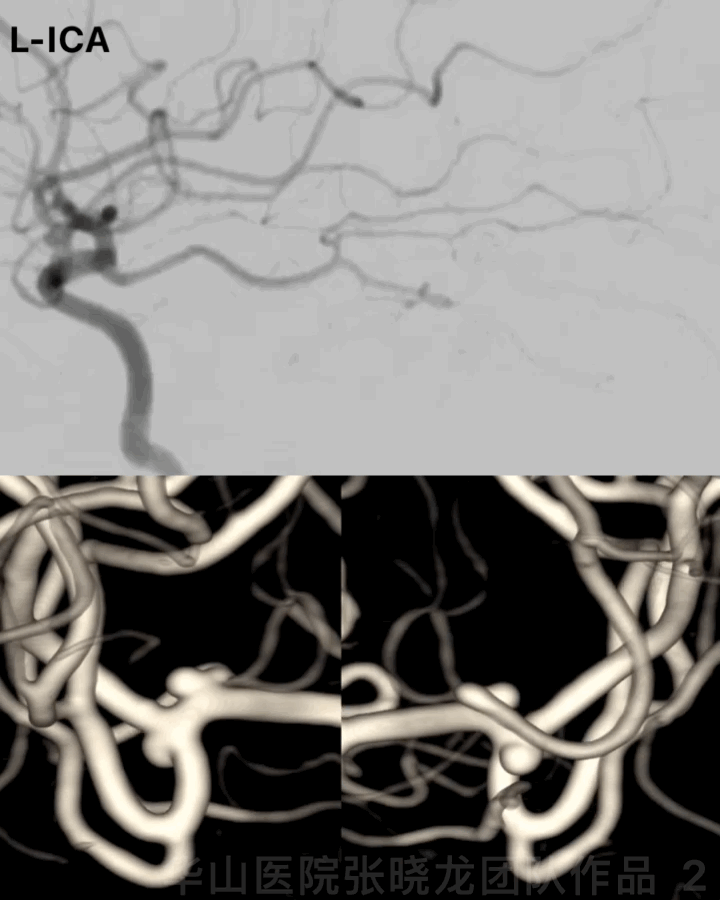

Figure 2 GIF. Two left middle cerebral artery aneurysms were visualized, with one incorporating the superior trunk and the other locating at the middle and inferior trunk bifurcation.

图 2 GIF. 造影证实左侧大脑中动脉2枚动脉瘤,一枚位于中动脉上干,另一枚位于中下干分叉部。

Figure 13. The left middle cerebral artery middle trunk straightened significantly by a Solitaire stent.

图 13. Solitaire支架将左侧大脑中动脉中干明显拉直。